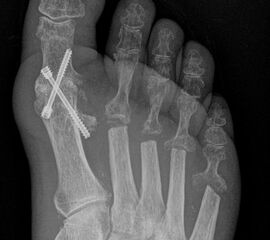

Deutlich bessere Ergebnisse wurden erreicht durch eine Kombination der OP nach Tillmann mit einer Arthrodese des Großzehengrundgelenks oder auch einer Lapidus-Arthrodese 611. Dies wurde bereits 1956 durch Vainio empfohlen, hat sich aber erst in diesem Jahrtausend flächendeckend durchgesetzt 121314.